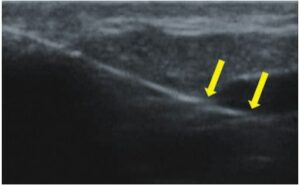

La ecografía Doppler permite obtener imágenes de grandes vasos y perforantes que suelen estar situados en las capas más profundas del tejido subcutáneo (fig. 1). Desgraciadamente, la ecografía convencional no es capaz de obtener imágenes de vasos más pequeños. Para visualizar los vasos más pequeños situados cerca de la superficie de la epidermis y en la capa superior del tejido subcutáneo, se utiliza el HFU (fig. 1). Gracias al uso de transductores con frecuencias superiores a 20 MHz, se obtiene una imagen ecográfica de alta resolución en la que podemos diferenciar estructuras menores de 0,1 mm. Sin embargo, cuanto mayor es la resolución, menor es la penetración del haz de ultrasonidos en las capas de la piel. Por lo tanto, dependiendo del transductor y del aparato, es posible penetrar en la piel hasta una profundidad de 20-30 mm como máximo. Tal penetración, junto con la alta resolución de la imagen, permite la evaluación incluso de vasos sanguíneos muy pequeños (fig. 2). Durante el examen con el uso de transductores de alta frecuencia, se puede evaluar con precisión el curso y la ubicación de los pequeños vasos en la piel. Esto es particularmente relevante para la selección del método de cierre del vaso y la planificación del procedimiento ya que, en la práctica, la superficie de la piel muestra muy a menudo únicamente un pequeño número de vasos o un ligero fragmento de un vaso; solo tras el examen por ecografía podemos determinar su número y curso reales. Para un cierre eficaz del vaso, es necesario hacerlo en toda su longitud. No debe limitarse al fragmento visto «a simple vista» en la superficie de la piel, ya que el cierre del fragmento causará su rápida recanalización(7). Con frecuencia, el vaso visible en la superficie de la piel cambia su curso, se vuelve más tortuoso y se desplaza a las capas más profundas de la piel(8). Por lo tanto, el curso de la vena y las perforantes deben conocerse y determinarse bien antes del procedimiento. El HFU también permite obtener imágenes de las perforantes entre pequeños vasos. Además, aparte de la evaluación del curso y la anatomía, la imagen ecográfica, gracias al software de ultrasonidos, también permite determinar los parámetros básicos como el diámetro del vaso, el grosor de su pared, la profundidad en la piel así como la presencia o ausencia de perfusión en el interior del vaso(6) (fig. 3). Gracias al transductor electrónico multielemento con la frecuencia de 40 MHz introducido en el mercado por Ultrasonix, también es posible visualizar la perfusión en los vasos en el modo Doppler color (fig. 4).